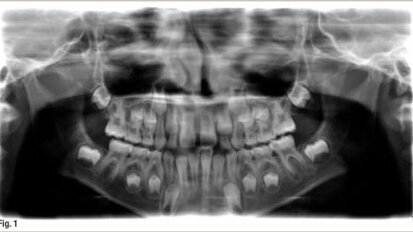

J'ai récemment reçu un e-mail, d'un dentiste généraliste, avec l'image de la dent 27 (image 1). Le mail : "j'ai une ...